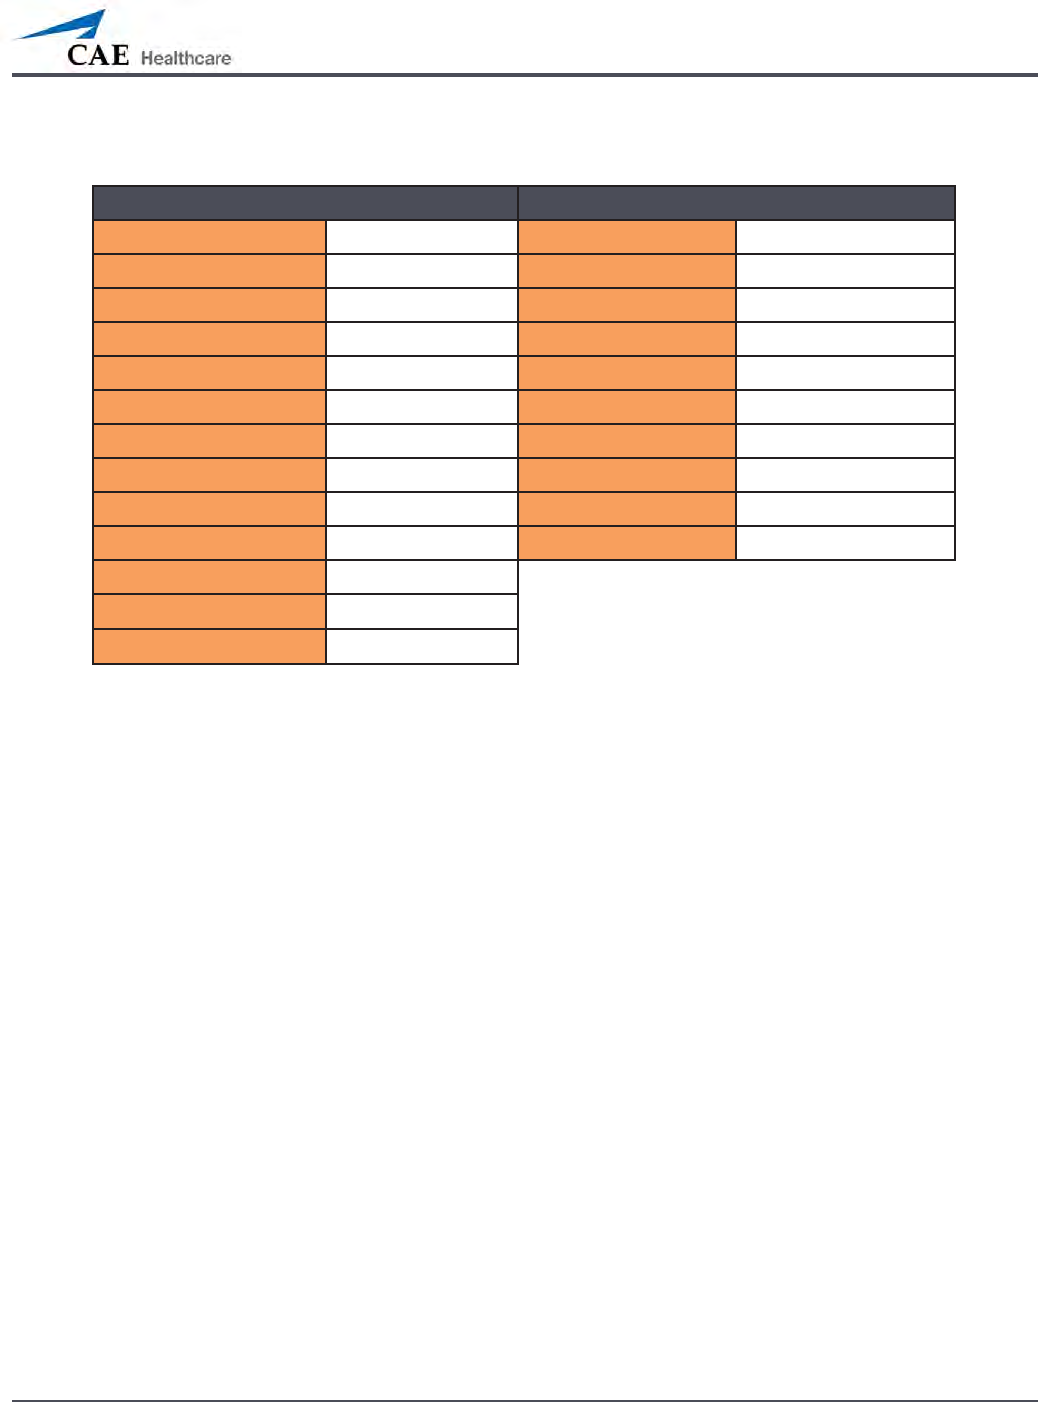

Pulmonary System

Anatomy,

Physiology and

Clinical Signs

Clinical Interventions, Patient Monitoring

and Scenarios.

Software Control

Manual Control

Spontaneous

Breathing

Normal tidal breathing and pathophysiological

conditions such as atelectasis, pneumothorax,

asthma and COPD.

None required, but

adjustable

VIEW: Respiratory

None required.

Exhaled CO2

(Prehospital only)

Measure the presence or absence of CO2 during

positive pressure ventilation.

None required. CO2 canister is

inserted

Pneumothorax or

Hemothorax

Increase in intrapleural volume, leading to

asymmetrical breathing.

None required, but

adjustable

VIEW: Respiratory

CONTROL: Intrapleural

Volume

(Left or Right)

None required.

Chest Excursion Synchronized with ventilation (spontaneous or

positive pressure ventilation). Excursion depth

proportional to tidal volume.

None required. None required.

Breath Sounds Normal and abnormal breath sounds are

independently synchronized with ventilation of

the right and left lungs. Breath sounds can be

auscultated over anterior and posterior anatomic

locations.

None required, but

adjustable

VIEW: Sounds

None required.

Bronchial

Occlusion

Completely obstructs right and/or left mainstem

bronchi, simulating a lower airway obstruction

(e.g. mucus plug). This yields an inability to

ventilate the lungs and asymmetric chest

excursion.

VIEW: Respiratory None required.

Pulse Oximetry Oxyhemoglobin saturation (SpO2) automatically

correlates with the oxygen concentration in the

lungs and the intrapulmonary shunt fraction.

None required, but

adjustable

SpO2 probe is

attached.

Arterial Blood

Gases

PaO2, PaCO2 and pH are continuously calculated,

and the Patient Status Display can be congured

to show them.

None required, but

adjustable

None required.

Venous Blood

Gases

PvO2 and PvCO2 are continuously calculated, and

the Patient Status Display can be congured to

show them.

None required, but

adjustable

None required.

139

Using METIman

Pulmonary System

Needle

Decompression

(Prehospital Only)

Decompression of a pneumothorax can be

performed bilaterally by inserting a needle at the

midclavicular line of the second intercostal space.

The instructor must

adjust the amount

of physiologic

intrapleural air present.

VIEW: Respiratory

CONTROL: Needle

Decompression,

Intrapleural Vol: Left,

Intrapleural Vol: Right

See Needle

Decompression

setup,.